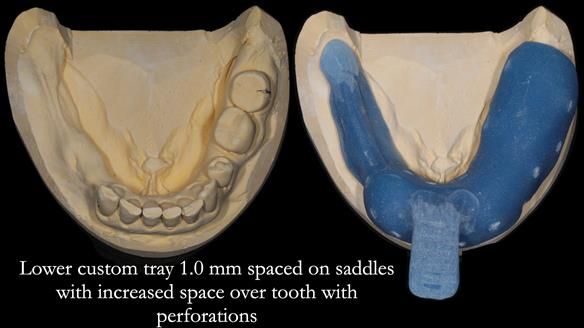

The detailed clinical situation and treatment process are outlined below, with clinical work provided by me and technical work by Rowan Garstang. The treatment spanned six visits for denture fitting and one review.